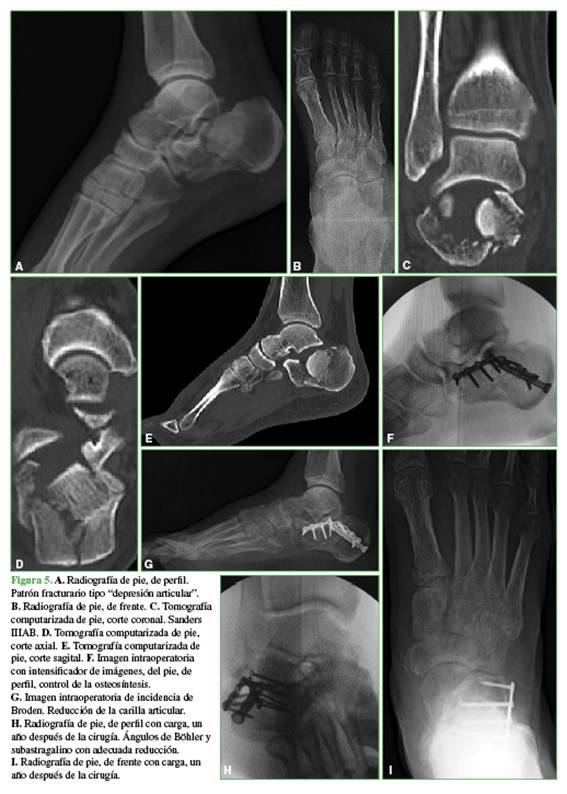

Se utiliza la superficie inferior del astrágalo como molde. Se colocan tornillos de 6,5 mm de rosca completa o parcial, corticales de 3,5 mm sin compresión desde la tuberosidad posterior hasta el fragmento medial y de 3,5 mm desde el fragmento superolateral hasta el medial (Figura 5).

Se colocan tornillos de 6,5 mm o 3,5 mm desde la tuberosidad posterior al proceso anterior. Pueden ser necesarios uno o dos tornillos adicionales desde el borde superior del fragmento superolateral hacia plantar en el patrón fracturario “en lengüeta” (Figura 6).

Se colocan placas de 2,7 mm o 3,5 mm bloqueadas desde el macizo articular hasta la tuberosidad anterior (Figura 7). Se toma una incidencia de Broden intraoperatoria con intensificador de imágenes para constatar la reducción de la faceta posterior y evaluar si hay brecha y escalón articular (Figura 8).14

El seguimiento promedio fue de 30.8 ± 23.2 meses. Ocho pacientes eran mujeres y 42, hombres. La edad era de 39.40 ± 14 años (rango 18-65). El mecanismo del trauma había sido una caída de altura (74%) y un accidente automovilístico (26%). El 2% eran fracturas expuestas y el 8% eran bilaterales. El patrón fracturario correspondió a los tipos “depresión articular” (63%) y “en lengüeta” (37%). Según la clasificación de Sanders, 40 fracturas eran tipo II (50% subtipo A; 42,5% subtipo B y 7,5% subtipo C); 13, tipo III (84,6% subtipo AC; 7,7% subtipo AC y 7,7% subtipo BC) y una, subtipo IV. El 37% tenía compromiso de la articulación calcaneocuboidea.

El puntaje de la escala de la AOFAS fue excelente en 12 pacientes, bueno en 25, regular en 12 y malo en cinco. El ángulo de Böhler era de 10,8 ± 10,4° antes de la cirugía, de 32,5 ± 7,73° (rango 22-54) en el posoperatorio inmediato y de 30,77 ± 8,24° (rango 17-54) a las seis semanas y al final del seguimiento. Esto valores fueron esta dísticamente significativos (p <0,00001) (Figura 9).